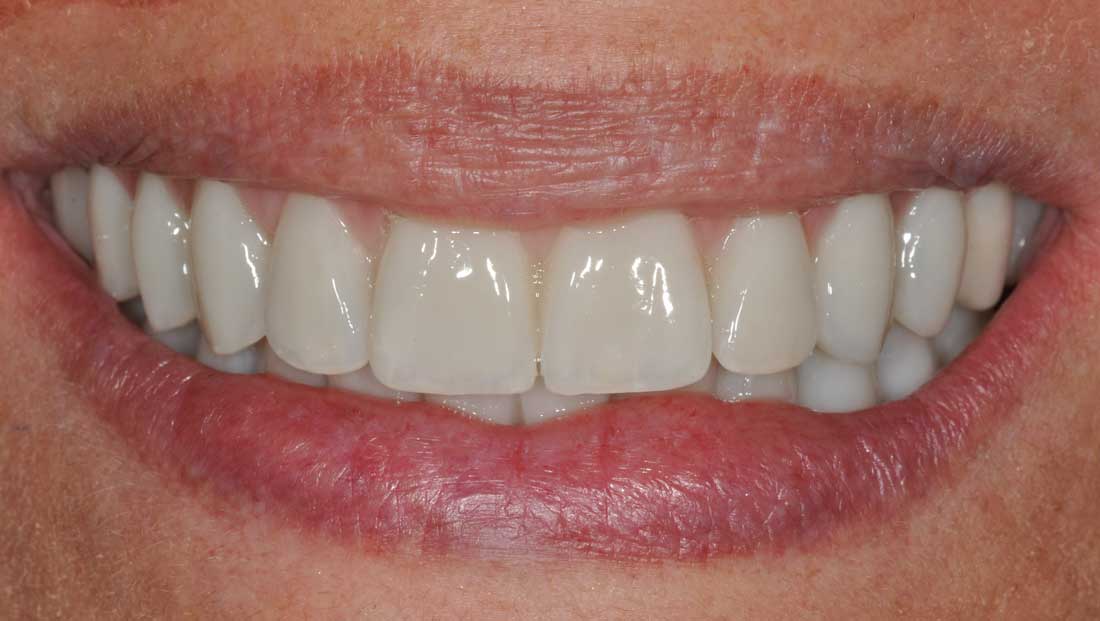

Alcuni casi clinici risolti con l'Implantologia (prima e dopo)

Con un'esperienza di oltre 20 anni pratichiamo nei nostri

due studi le seguenti tecniche d'implantologia:

Protesi fissa estetica su impianti e denti naturali (*)

(*)quando possibile recuperiamo i denti naturali rispettando i principi etici e deontologici ripristinando sorrisi meravigliosi.

Il successo nel tempo degli impianti dentali dipende oltre che dal lavoro del dentista implantologo anche dalla qualità e dalla tipologia del lavoro protesico; pertanto consapevoli di ciò e servendoci dell’eccellenza dei laboratori odontotecnici italiani eseguiamo e garantiamo le seguenti tipologie di protesi fisse su impianti e denti naturali:

- protesi fissa in zirconia monolitica

- protesi fissa in zirconia ceramica

- protesi fissa in metallo ceramica

- protesi fissa in metallo composito